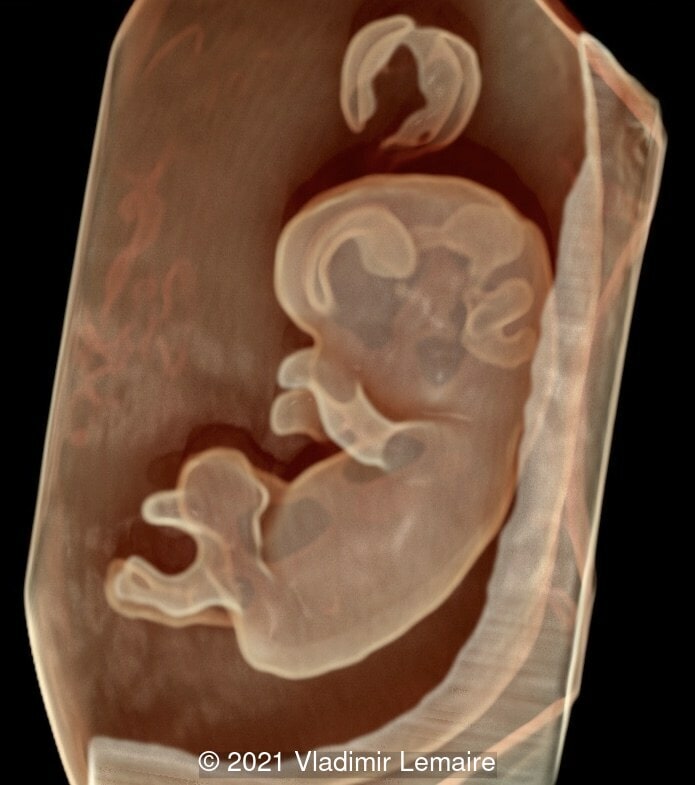

Image obtained by augmenting the transparency effect and adjusting light effects.

Image 4 Image obtained by augmenting the transparency effect and adjusting light effects.